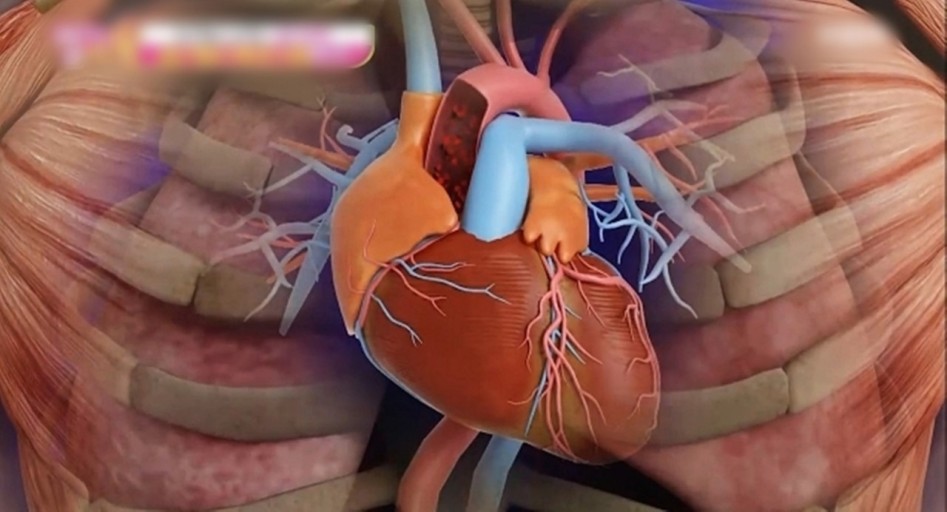

오늘은 정말 많은 분들이 놓치기 쉬운 **치명적인 심장 질환, ‘심근경색’**에 대해 이야기해보려 합니다.심근경색은 말 그대로 심장 근육이 괴사하는 질환으로, 골든타임을 놓치면 생명을 잃을 수 있는 응급상황입니다.

심장 혈류가 막히는 순간, 몸이 위급 상황으로 인식하여 자율신경 반응으로 식은땀을 흘리게 됩니다.

심장 기능이 급격히 떨어지면 혈압이 내려가고, 얼굴과 손끝이 창백하거나 푸르스름해질 수 있습니다.

이는 심정지로 이어지는 응급 상황일 수 있으므로 즉시 119 또는 응급실로 이동해야 합니다.심근경색 주의사항